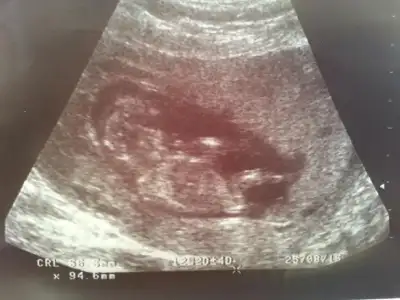

Canım ilk fotografa bakmamıştım bebek tam yan değil hafif arkası dönük sidellanın tahmini doğru sanırım...Cnm bidaha baksana ya,sidella2011 nub yan yatmis kiz dedi..

Cnm bu en son foto 13+6, bunada baksana daha net bu foto..Canım ilk fotografa bakmamıştım bebek tam yan değil hafif arkası dönük sidellanın tahmini doğru sanırım...